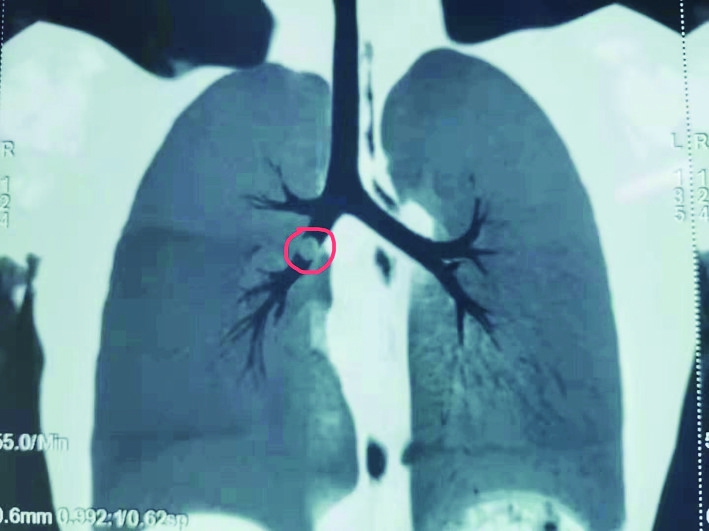

支气管镜下发现异物不完全阻塞左主支气管.

左主支气管内异物取出过程中.